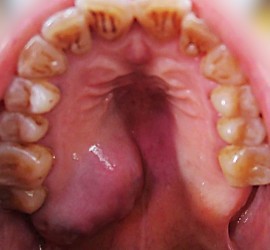

Аденокарцинома — злокачественные эпителиальные опухоли, образующие железистые и папиллярные структуры, но не имеющие характерных признаков других видов рака слюнных желез. Возникают как в больших, так и в малых слюнных железах. Гистологически связаны с протоками слюнных желез. Наиболее характерные морфологические признаки аденокарциномы слюнных желез — пролиферация эпителия в протоковых образованиях в виде […]